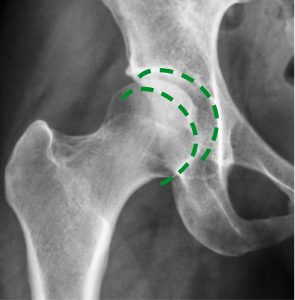

Снимката вляво (направена преди терапията) показва дефицит на синовиална течност, която причинява костна абразия. На снимката вдясно, благодарение на терапията, костите се движат плавно и безболезнено. Структурата на синовиалната течност се е възстановила – тя е възвърнала плъзгащите си свойства.

Зиглер доказа (както се вижда от рентгенови лъчи и ултразвук), че неговата антиартритна формула влияе върху регенерацията на ставите на три основни нива: